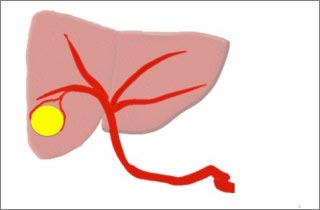

図1

カテーテル(細い管)から動脈に造影剤を流して写真を撮り、腫瘍に栄養を送る動脈を見つけます。